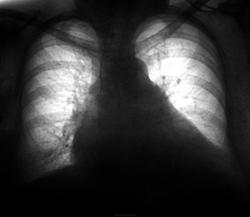

Флюшка ровно через год...

Через год пациентку на носилках доставили в рентгеновкий кабинет... для рентгенографии ОГК, а в истории болезни "ни слова" по поводу предыдущих исследований...

Что самое интересное, что после "первого" выявления распространенных метастазов (рентгенологически), не поверили и направили пациента на МРТ.

Потом усомнились в МРТ и направили снова на "рентген".

По всей видимости, такое положение не только а нашей глубокопериферийной больничке...